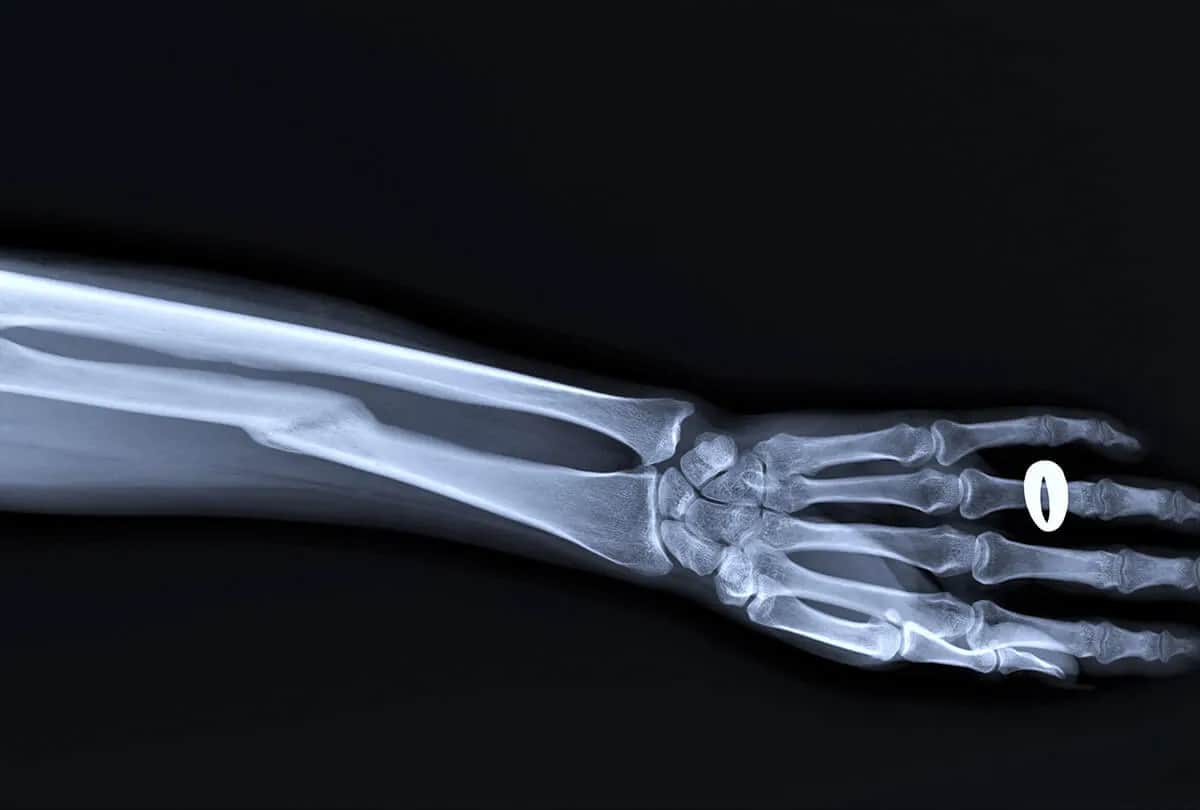

- Diagnostyka obejmuje wywiad, badanie fizykalne i obrazowe